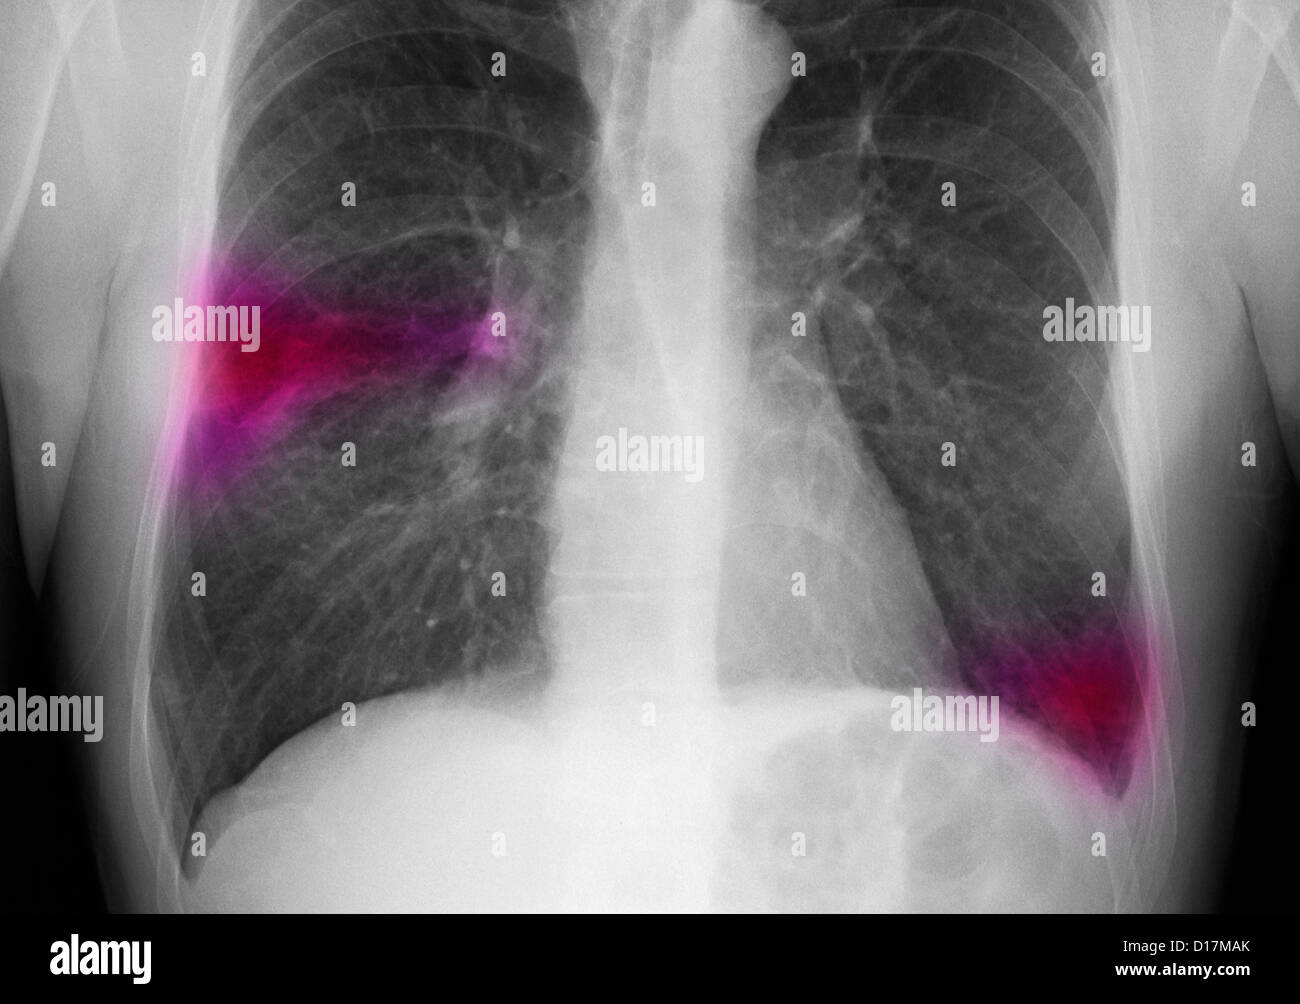

Chest Xray of man with infiltrate in right lung Stock Photo 52415403 Types Of Infiltrates On Chest X Ray from a pathophysiological perspective, the term infiltrate refers to “an abnormal substance that accumulates gradually. from a pathophysiological perspective, the term infiltrate refers to “an abnormal substance that accumulates. persistent pulmonary infiltrate results when a substance denser than air (e.g., pus, edema, blood, surfactant,. it can be argued that a chest ct scan should be performed. Types Of Infiltrates On Chest X Ray.